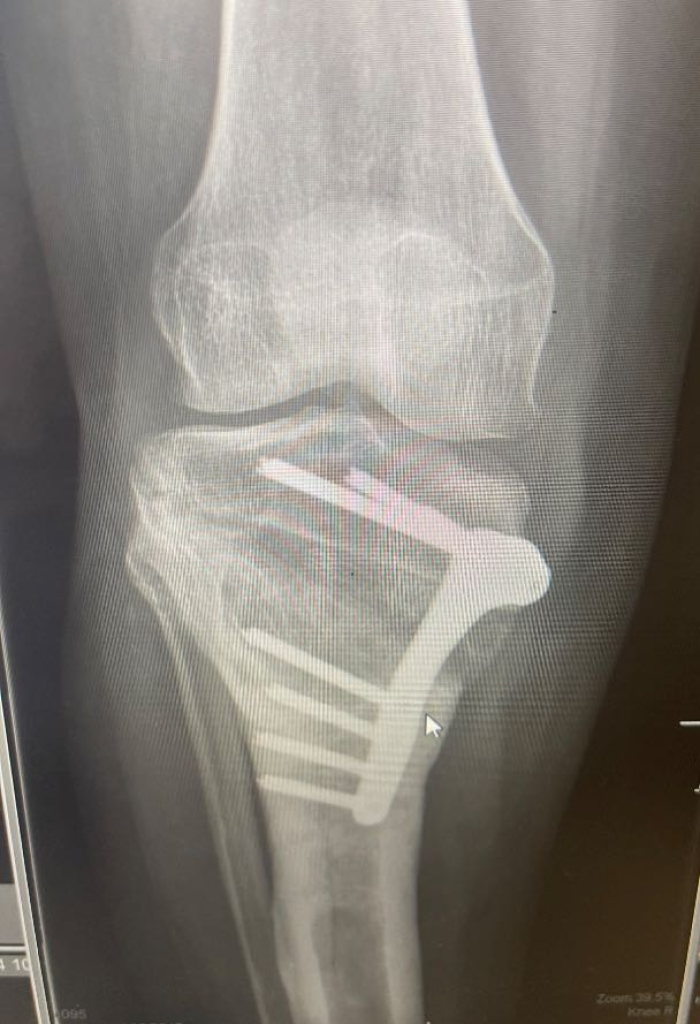

Tibial osteotomy - (5-50)

Open surgical stabilisation of patella, including soft tissue/tendon transfer or release, +/- application of cast (adult) - (1-5)

Removal of internal fixation from bone / joint, excluding K-wires +/- image guidance - (1-5)